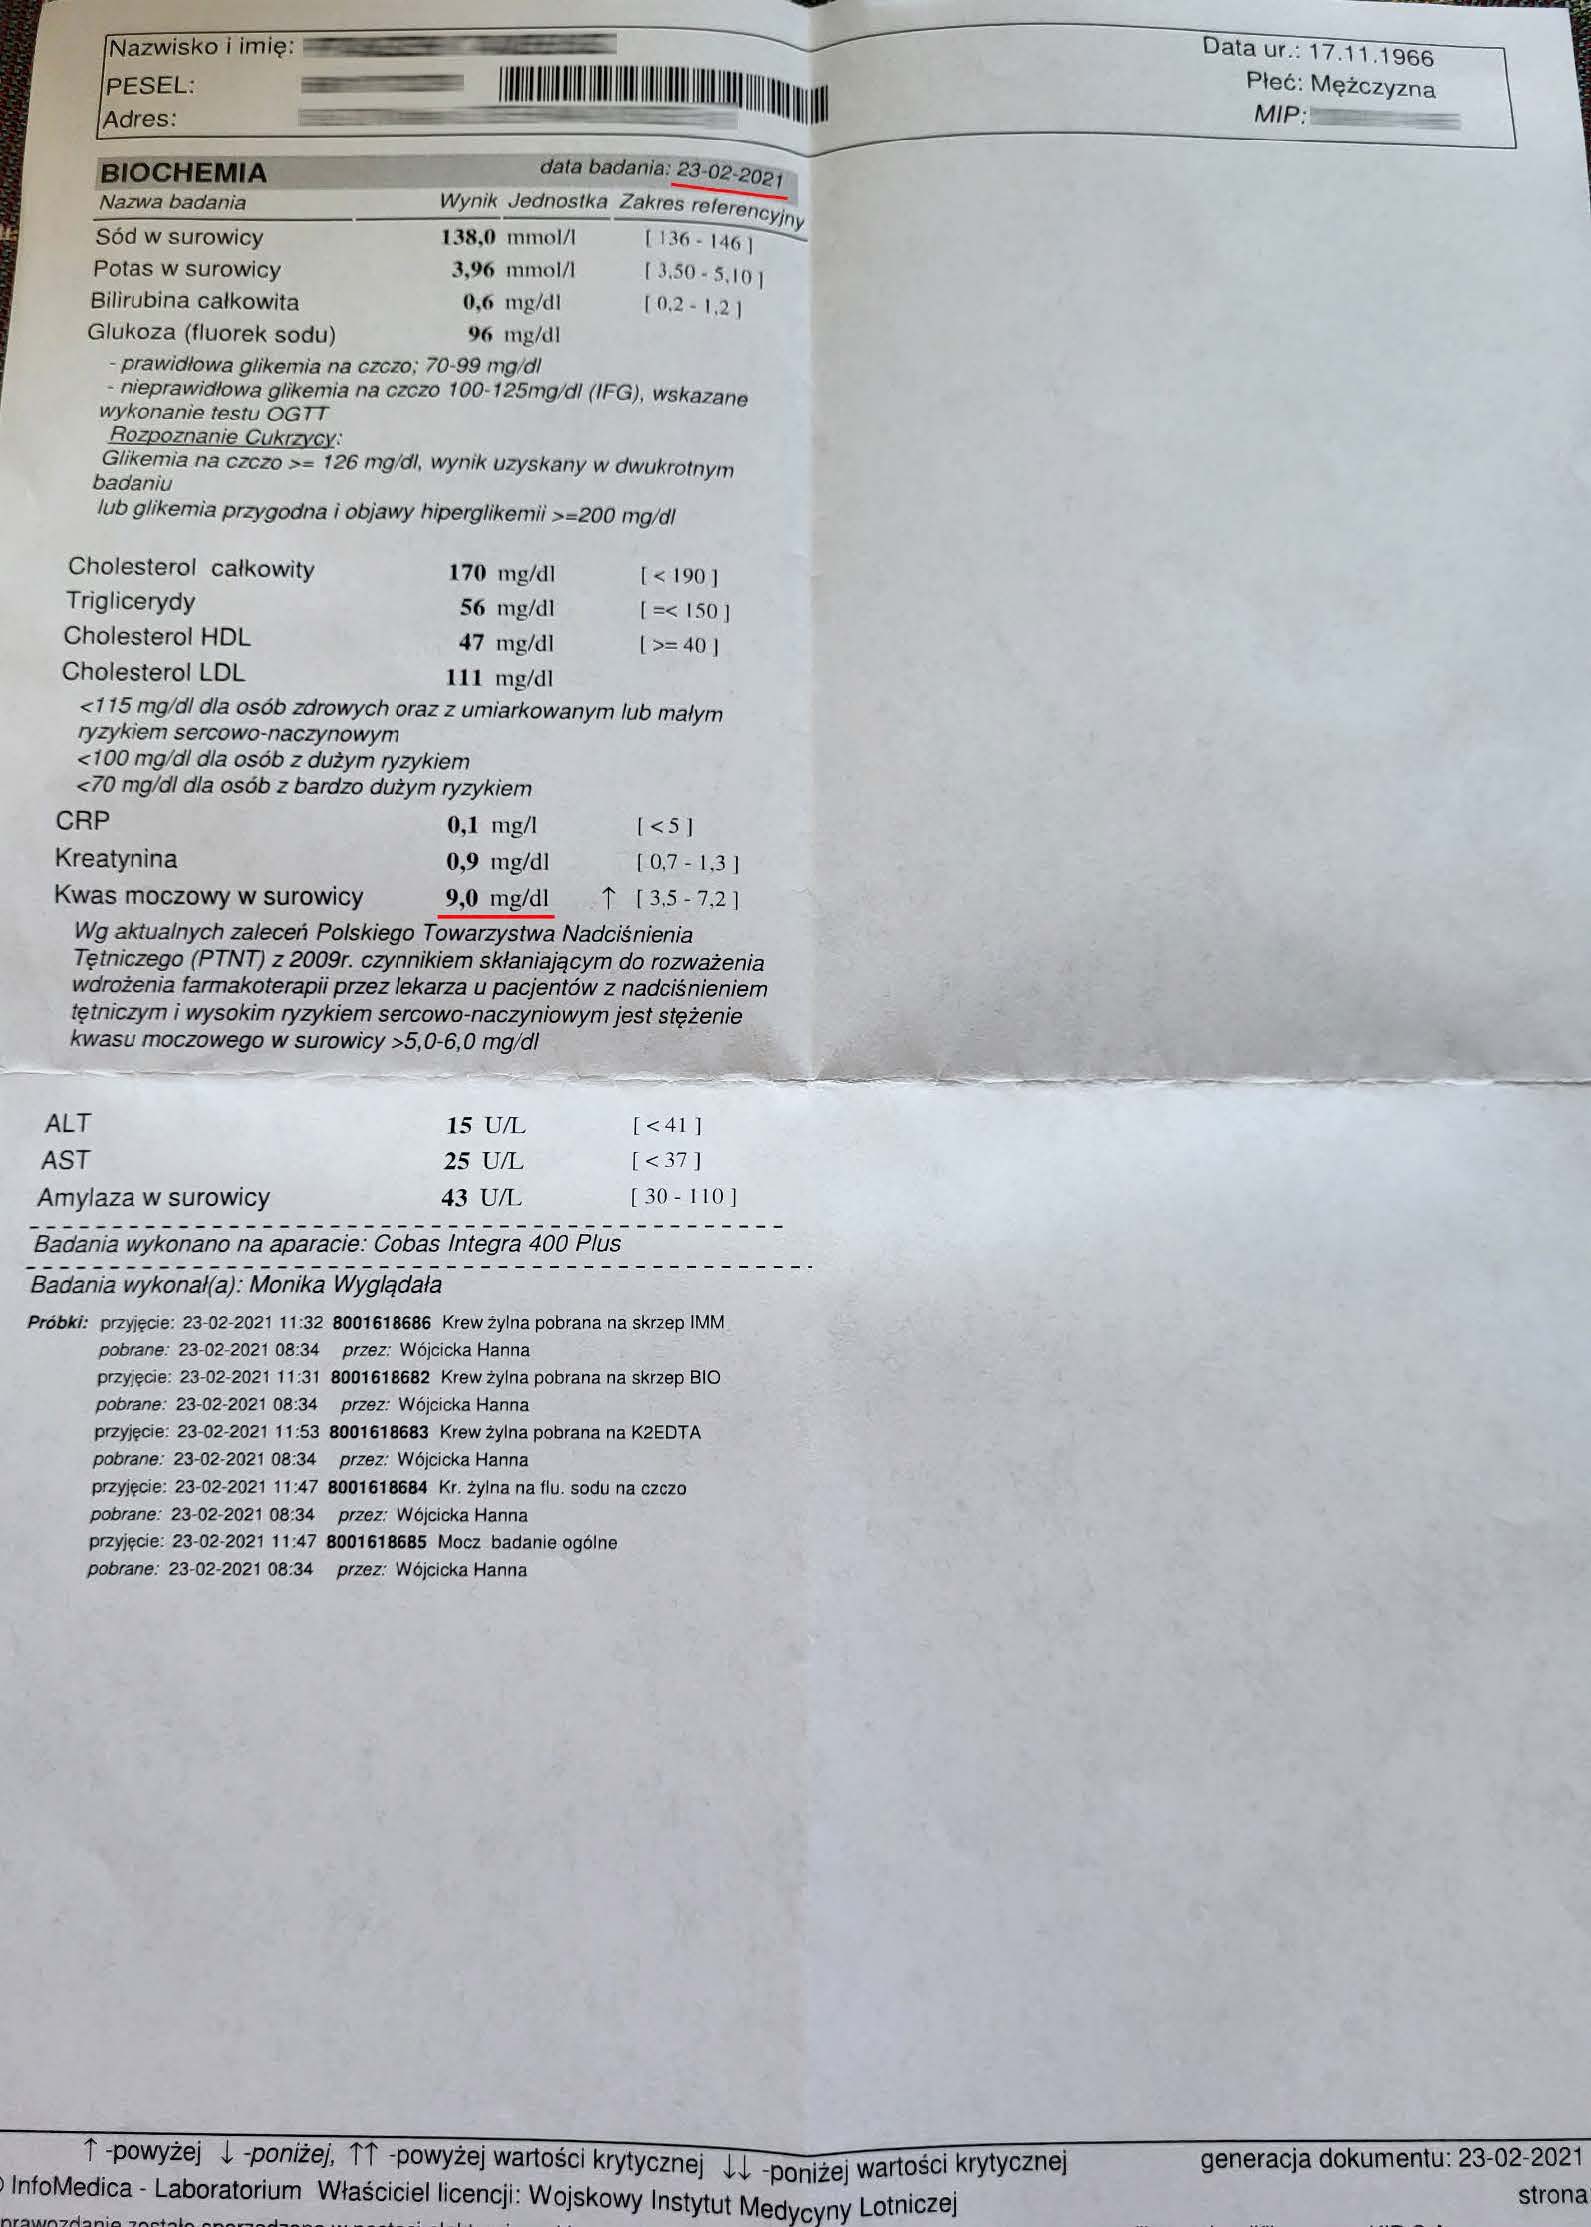

EFEKT PREPARATU NA PODAGRĘ

Dna moczanowa u 56 letniego mężczyzny, diametralny spadek kwasu moczowego. Wartość przed terapią 9,0 mg/dl towarzyszące cykliczne ataki dny , historia choroby zaczęła się jednak znacznie wcześniej niż data pierwszego badania. W roku 2022 rozpoczęto terapię preparatem i po 3 miesiącach stosowania odnotowano spadek kwasu moczowego do 7,9 mg/dl , natomiast po stosowaniu przez następne 6 miesięcy ilość kwasu moczowego obniżona została do poziomu 3,6 mg/dl, wraz z obniżeniem poziomu kwasu moczowego do pożądanego poziomu ustały ataki dny, efekt utrzymuje się trwale. Redukcja o 60% kwasu moczowego pokazuje odwrócenie nagromadzeń moczanowych. Preparat zwiększa ATP mitochondrialny w komórkach nerek i wątroby, poprawiając metabolizm puryn i filtrację, co usuwa kryształy moczanu i wycofuje zapalenie stawów. Standardowe leczenie allopurynolem i kolchicyną wymaga dożywotniego leczenia obarczonego skutkami ubocznymi, które wpływają na codzienne funkcjonowanie, w przypadku preparatu brak skutków ubocznych i relatywnie szybka odpowiedź organizmu.